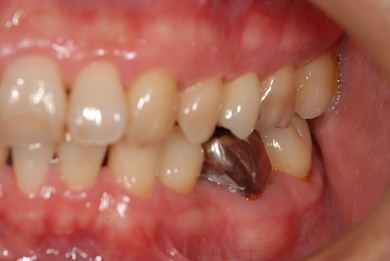

| 性別/年齢 | 男性 / 37歳 | ||||||||||||||||||||||||||||||||

| 治療方針 | 右下欠損部分をインプラント治療にて、機能的・審美的回復を行う。 | ||||||||||||||||||||||||||||||||

| 治療内容 | インプラント1本、メタルボンドセラミッククラウン1本 | ||||||||||||||||||||||||||||||||

| 総治療費 | 252,000円 | ||||||||||||||||||||||||||||||||

| 治療期間 | 7ヶ月 |